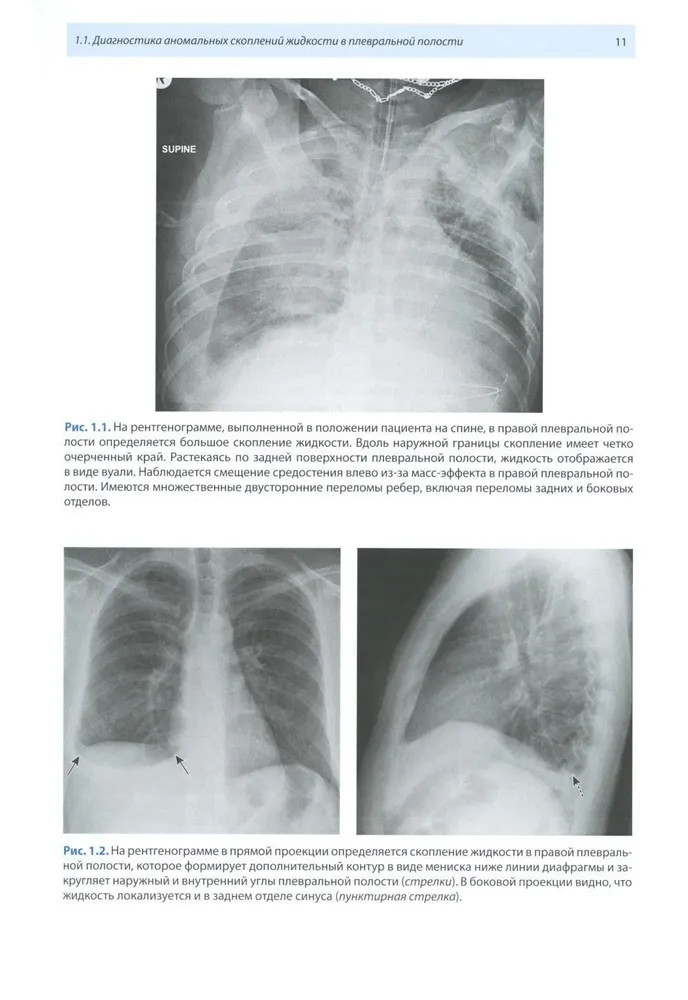

💳 Оплатить за товар можно при получении 🇰🇿 Есть бесплатная доставка по Казахстану от 1 дня 🎁 Копите бонусы с каждой покупки Издание содержит результаты анализа многочисленных рентгенологических и КТ-исследований, выполненных с целью диагностики огнестрельных ранений грудной полости. Уделено большое внимание описанию макроморфологических изменений при современной огнестрельной травме, отображаемых при КТ, и патогенезу их развития. Описана рентгеновская семиотика ранений легких, пищевода, сердца, сосудов, а также наиболее грозных осложнений, встречающихся при ранениях этих органов. Наряду с обычным рентгенологическим методом и КТ показаны возможности современных информативных медицинских технологий в диагностике боевой травмы. Книга иллюстрирована большим количеством рентгенограмм и КТ-изображений. Авторы надеются, что предлагаемая монография будет интересна врачам-рентгенологам, а также врачам других специальностей, занимающимся проблемами диагностики и лечения огнестрельных ранений. |